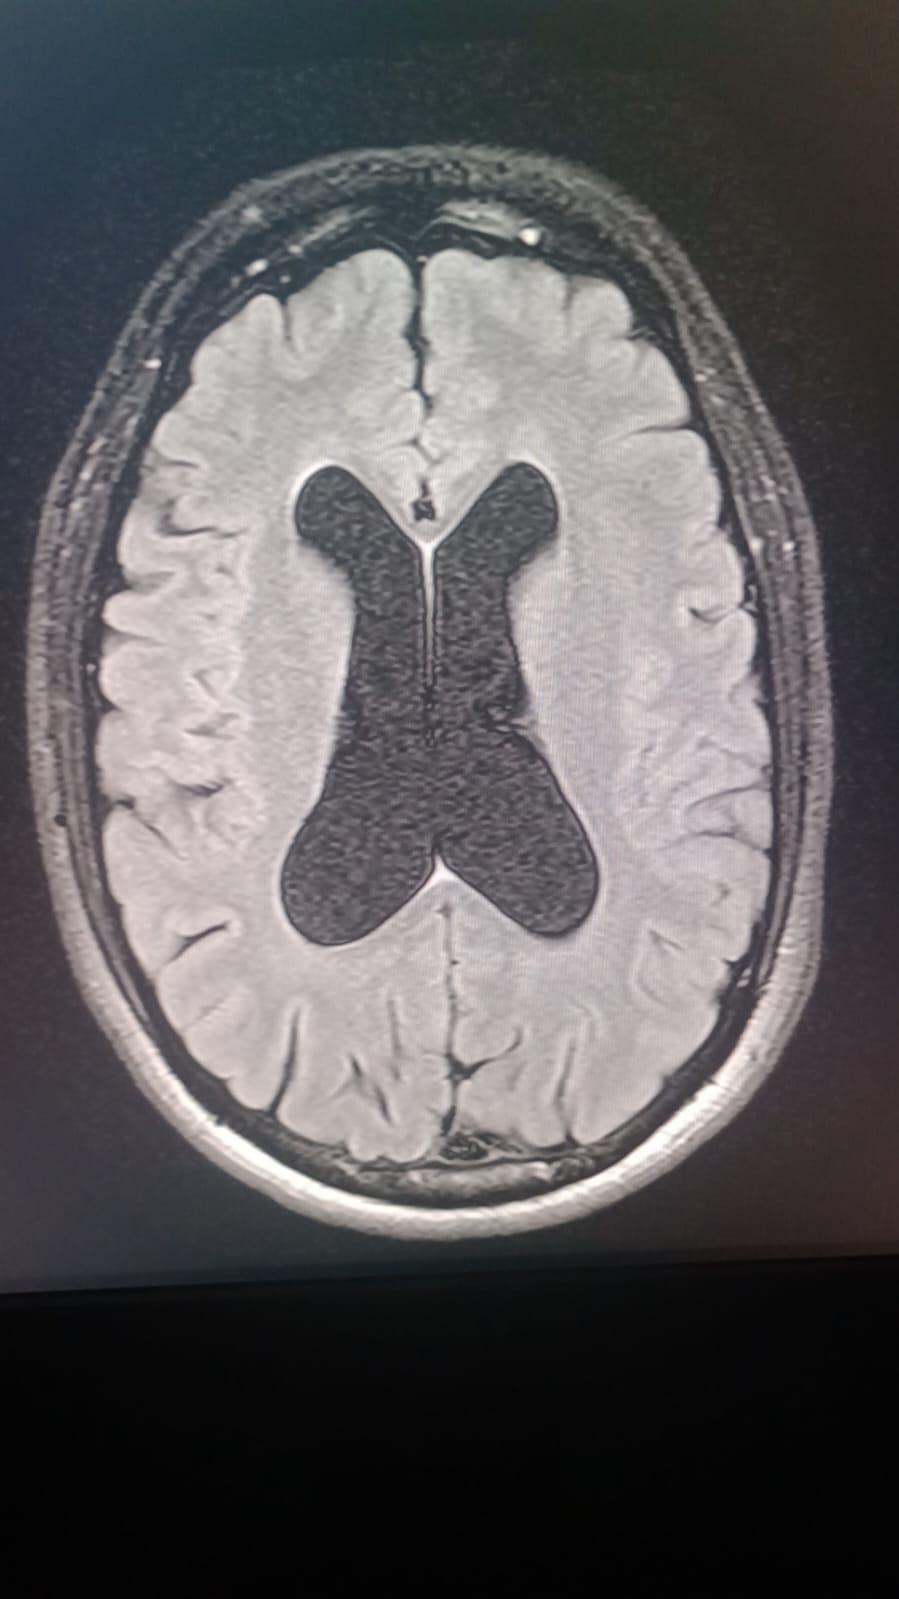

Our dear Cesar Eduardo Rodríguez Ortiz has been fighting seizures since he was just two years old, after suffering a head injury as a baby. Despite years of struggle, his strength and spirit have never faded.

On October 17, 2025, Cesar underwent a major brain surgery to help control his severe epilepsy. By God’s grace, the surgery went well, and he is now beginning his road to recovery.